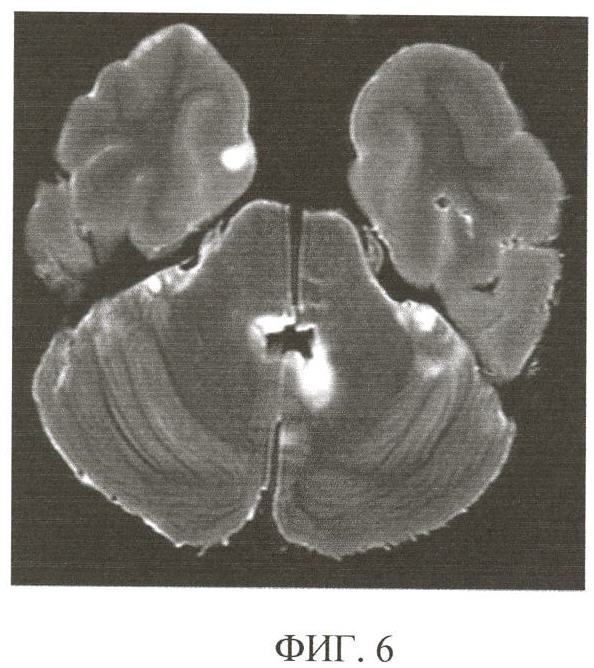

Пример 2. Б-ная (И.б. 2700-06, РНХИ) 26 лет была прооперирована по поводу астроцитомы спинного мозга на уровне Th1-7. В дальнейшем на фоне нарастания неврологической симптоматики при проведении МРТ головного мозга признаки объемного очагового поражения отсутствовали. Причины клинического ухудшения вплоть до момента смерти не были ясны. Согласно заявляемому способу при посмертной МРТ головного мозга обнаружен опухолевый субстрат, выстилающий стенки IV желудочка, его сигнальные характеристики соответствовали ликвору: гиперинтенсивный на Т2 ВИ, гипоинтенсивный на Т1 ВИ. Кроме того, выявляются лептоменингеальные мелкие очаги преимущественно в задней черепной ямке (фиг.6). При макроскопическом исследовании солидная ткань опухоли представляет собой бугристые разрастания в полости IV желудочка, но изменения оболочек мозжечка не определяются (фиг.7). При гистологическом исследовании очагов измененного МРТ сигнала на оболочках мозга выявлены метастазы полиморфноклеточной глиобластомы (фиг.8).

Ретроспективный анализ клинической картины, результатов прижизненного МРТ и заявленного способа комплексного посмертного паморфологического исследования позволил заключить, что стелющийся диффузный рост опухоли вместе с ее сигнальными характеристиками, соответствующими ликвору, привел к отсутствию признаков объемного поражения головного мозга при прижизненном МРТ исследовании. Значительная распространенность и характер опухолевого процесса, выявленного заявленным способом комплексного посмертного патоморфологического исследования, позволили диагностировать злокачественный глиоматоз спинного и головного мозга с метастазами по мозговым оболочкам.